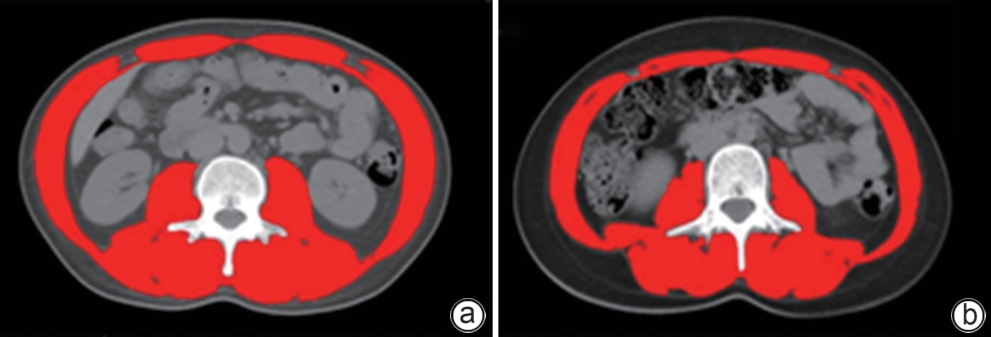

Establishment and validation of a risk prediction model for 90-day mortality in patients with acute-on-chronic liver failure based on sarcopenia

Huina CHEN, Ming KONG, Siqi ZHANG, Manman XU, Yu CHEN, Zhongping DUAN

2025, 41(6): 1135-1142. DOI: 10.12449/JCH250620

Abstract(1037) HTML (304) PDF (2616KB)(66)

Abstract:

Objective  To establish and validate a new prediction model for the risk of death in patients with acute-on-chronic liver failure (ACLF) based on sarcopenia and other clinical indicators, and to improve the accuracy of prognostic assessment for ACLF patients.  Methods  A total of 380 patients with ACLF who were admitted to Beijing YouAn Hospital, Capital Medical University, from January 2019 to January 2022 were enrolled, and they were divided into training group with 228 patients and testing group with 152 patients in a ratio of 6∶4 using the stratified random sampling method. For the training group, CT images were used to measure the cross-sectional area of the skeletal muscle at the third lumbar vertebra (L3), and L3 skeletal muscle index (L3-SMI) was calculated. Sarcopenia was diagnosed based on the previously established L3-SMI reference values for healthy adults in northern China. Univariate and multivariable Cox regression analyses were used to establish a sarcopenia-ACLF model which integrated sarcopenia and clinical risk factors, and a nomogram was developed for presentation. The area under the ROC curve (AUC) was used to assess the predictive performance of the model, the calibration curve was used to assess the degree of calibration, and a decision curve analysis was used to investigate the clinical application value of the model. The independent-samples t test or the Mann-Whitney U test was used for comparison of continuous data between two groups, and the chi-square test was used for comparison of categorical data between two groups. The Kaplan-Meier method was used to plot survival curves, and the Log-rank test was used for comparison between groups. The DeLong test was used for comparison of AUC between different models.  Results  The multivariate Cox regression analysis showed that sarcopenia (hazard ratio [HR]=1.962, 95% confidence interval [CI]: 1.185‍ ‍—‍ ‍3.250, P=0.009), total bilirubin (HR=1.003, 95%CI: 1.002‍ ‍—‍ ‍1.005, P<0.001), international normalized ratio (HR=1.997, 95%CI: 1.674‍ ‍—‍ ‍2.382, P<0.001), and lactic acid (HR=1.382, 95%CI: 1.170‍ ‍—‍ ‍1.632, P<0.001) were included in the sarcopenia-ACLF model. In the training cohort, the sarcopenia-ACLF model had a larger AUC than MELD-Na score in predicting 90-day mortality in patients with ACLF (0.80 vs 0.73, Z=1.97, P=0.049). In the test cohort, the sarcopenia-ACLF model had a significantly larger AUC than MELD score (0.79 vs 0.69, Z=2.70, P=0.007) and MELD-Na score (0.79 vs 0.68, Z=2.92, P=0.004). The calibration curve showed that the model had good calibration ability, with a relatively good consistency between the predicted risk of mortality and the observed results. The DCA results showed that within a reasonable range of threshold probabilities, the sarcopenia-ACLF model showed a greater net benefit than MELD and MELD-Na scores in both the training cohort and the test cohort.  Conclusion  The sarcopenia-ACLF model developed in this study provides a more accurate tool for predicting the risk of 90-day mortality in ACLF patients, which provides support for clinical decision-making and helps to optimize treatment strategies.